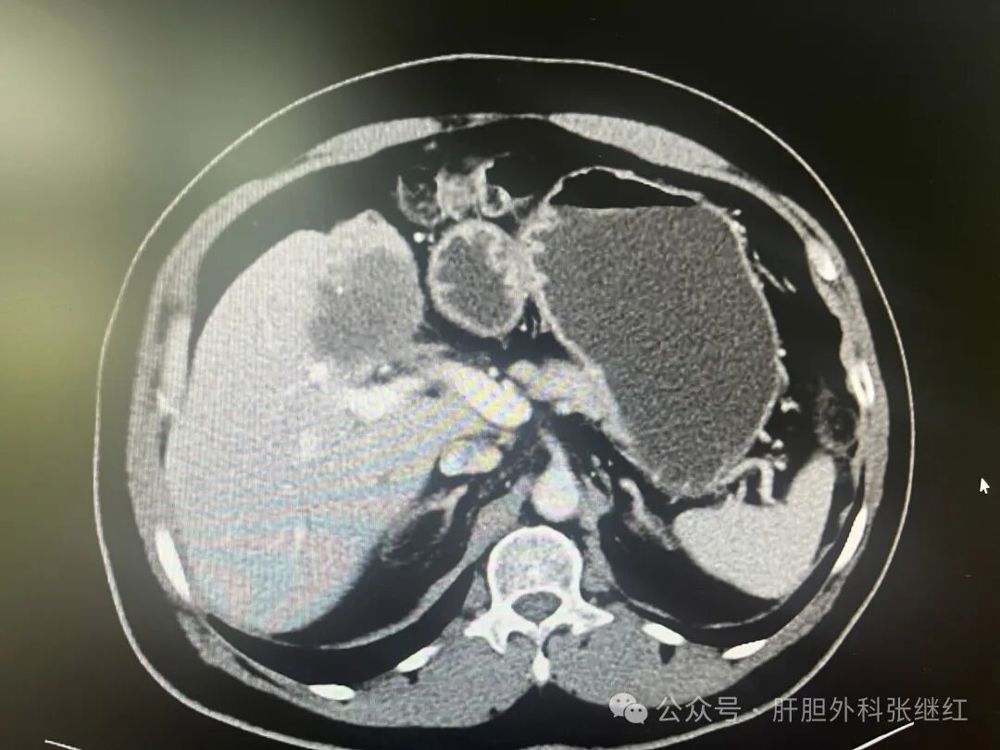

该患者是佛山复星禅诚医院肝胆胰外科病例,张继红医生有幸参加了术前多学科会诊和手术。1年前,一男性56岁病人,经CT、MR等影像学检查和病理活检确诊为胆管细胞癌,瘤体巨大,长径超过10厘米,且伴门静脉左支癌栓形成和多发腹腔淋巴结转移,经多学科会诊后决定应用吉西他滨和奥沙利铂化疗联合PD-L1单抗(度伐利尤单抗)免疫治疗进行转化治疗后再手术切除。经上述化疗联合免疫治疗五个疗程(每次均为单次给药,间隔时间21天)治疗后肿瘤明显缩小,直径约5厘米,淋巴结病灶也有所减少或缩小,达到了影像学部分缓解和手术切除的标准,经多学科会诊后决定行扩大左半肝切除及区域淋巴结清扫术,术后再行辅助治疗。本为腹腔镜手术,术中见左肝肿瘤萎缩明显,肿瘤压迫右侧肝蒂,肝门部及肝总动脉周围未见明显肿大淋巴结,肝门部粘连严重,仅清扫12a、12b、7-9组淋巴结所在区域脂肪淋巴组织,解剖离断左肝动脉、门静脉左支及左肝管,发现肿瘤基本位于缺血范围内,超声引导下在缺血线和S5段肿瘤外侧画切肝线,拟切除包括胆囊的S5段和左半肝,15+5min模式间歇性阻断肝门,沿预切线离断肝实质,达右肝蒂时发现肿瘤紧贴右肝蒂,为避免右肝蒂损伤,中转开腹完成整块切除包括胆囊的S5段及左半肝。手术后病理证实肿瘤100%坏死,清扫淋巴结亦未发现肿瘤细胞,达到病理学完全缓解(pCR)。术后早期肝断面少许积液,经引流后积液消失。目前病人状态良好,已无瘤生存半年余。

45703dca33d74568b7f2ab02bd8694b0.jpg  手术前三维重建